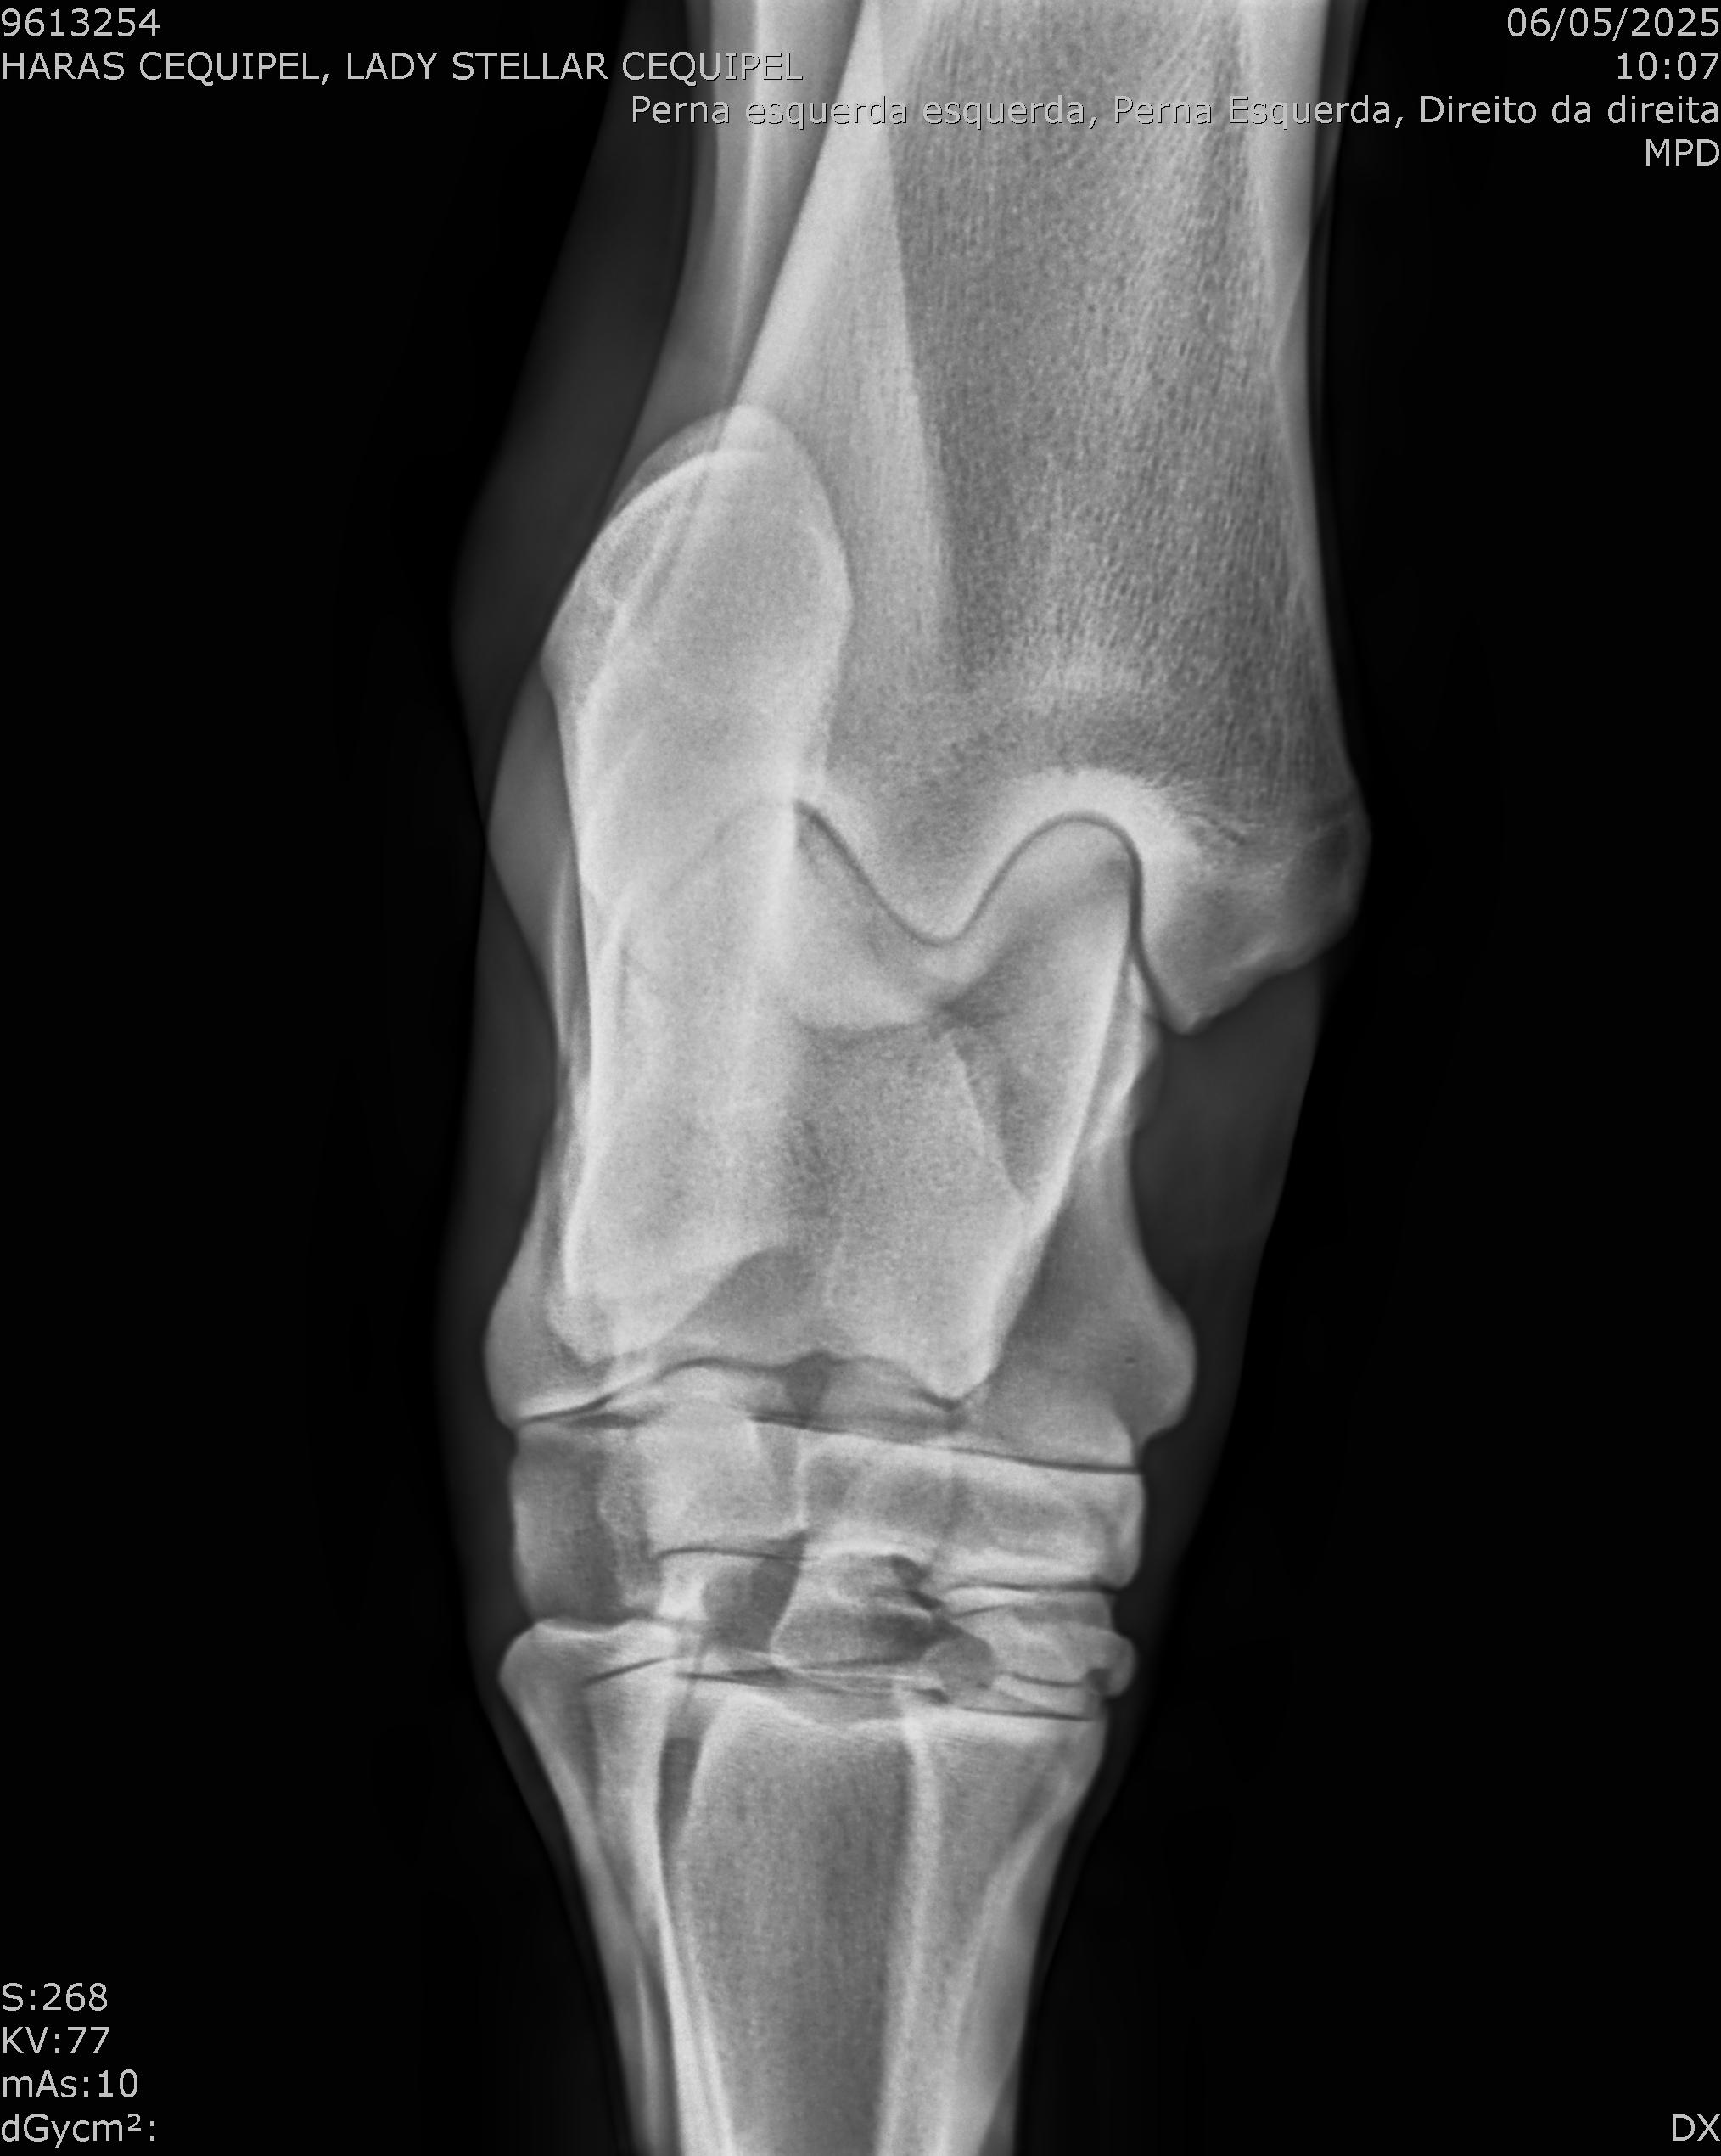

:: RAIOS-X DO LOTE